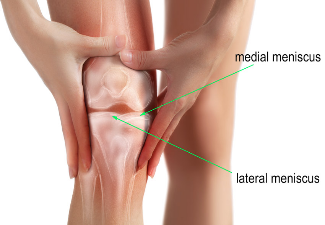

Three bones meet to form your knee joint: your thighbone (femur), shinbone (tibia), and kneecap (patella). There are two pieces of shock-absorbers between the thigh bone and the leg bone. These are called meniscus. They are tough and rubbery to help cushion the joint and keep it stable.